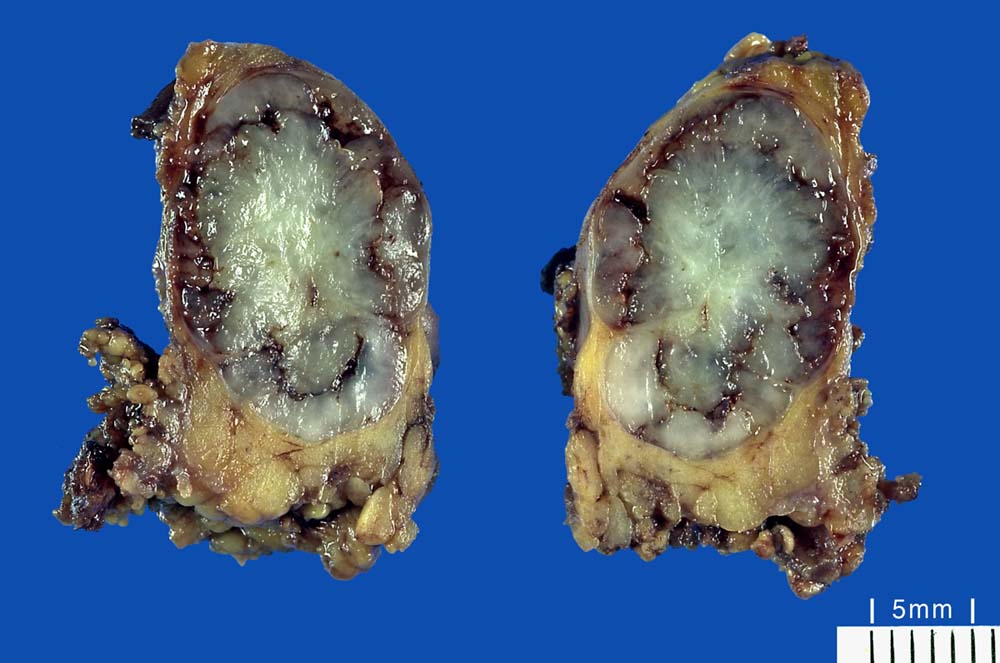

Makroskopie:

Makroskopisch sind pleomorphe Adenome scharf begrenzt. In den grossen Speicheldrüsen sind die meist solitär wachsenden Knoten von einer Kapsel umgeben, nicht aber in den kleinen Speicheldrüsen. Rezidivtumoren bilden oftmals multiple Knoten.

Makroskopie

Befund

Pathologischer Befund